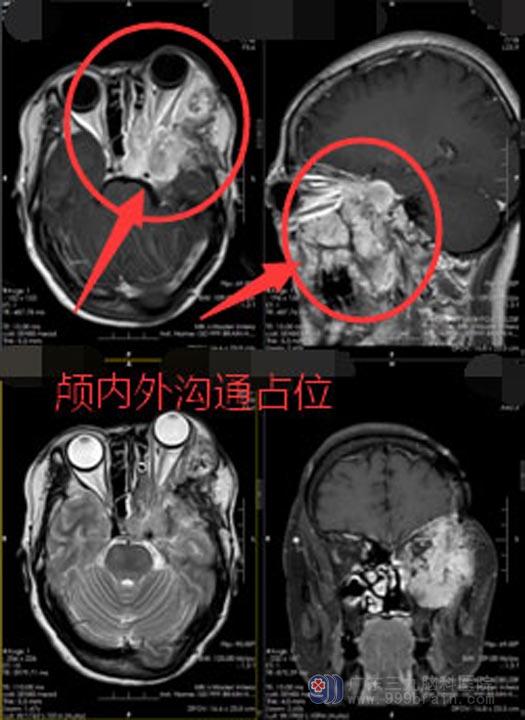

蔡阿姨因左眼突出伴颜面肿胀,1年前在外院行左颞部颅内外沟通脑膜瘤切除手术。去年 11月份再次出现左眼突出伴颜面肿胀、左眼无光感伴肿胀、轻微闭合不全。在之前的手术医院复查,MRI结果提示:脑膜瘤切除术后复发。

入住广东三九脑科医院神经外五科后,蔡阿姨进一步的检查结果显示:“左侧前中颅底及左侧颌面部颅内外沟通复发脑膜瘤”。